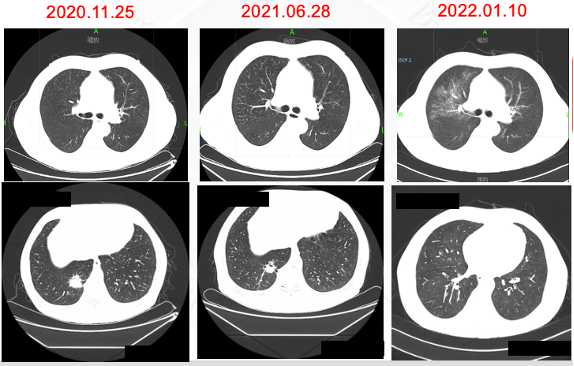

方案:2021.06行胸部放疗55Gy/5次。

√ 2021.06.28胸部CT:右肺下叶后基底段肿块约21×23×21mm大小,右肺下叶后基底段(Img230)见结节影,大小为7×7mm,较前缩小。疗效评价PR。

图7胸部CT